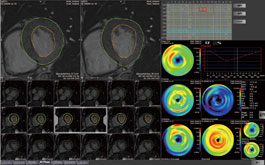

MR Cardiac Function

Utilizing multi-phase MR images of the heart, this protocol segments the inner and outer walls of the left ventricle, and calculates ejection fraction, wall thickness, wall thickness ratio and regional wall motion.

Utilizing multi-slice CT images of the heart, this protocol segments the inner and outer walls of the left ventricle, and calculates ejection fraction, wall thickness, wall thickness ratio and regional wall motion.